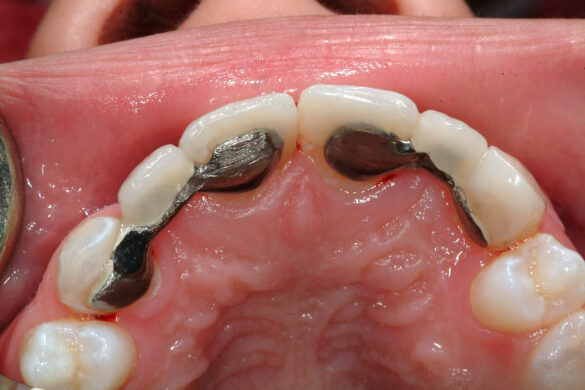

În aprilie 2009, după 37 luni de tratament, au fost îndepărtate aparatele fixe (fig. 6). Pentru contenţie, s-a aplicat un retainer fix colat pe faţa linguală a celor şase dinţi frontali inferiori şi o placă palatinală Hawley care încorporează dinţi acrilici în dreptul incisivilor laterali pentru a menţine un aspect estetic până când medicul protetician va putea realiza punţile dentare. În plus, s-a utilizat un arc vestibular care să consolideze contenţia şi care să permită aplicarea unor forţe uşoare, cu direcţie linguală, dacă este necesar.25 Croşetele ”în deget” sunt situate distal de incisivii centrali maxilari şi mezial de caninii superiori, pentru a permite o deplasare discretă mezio-distală a dinţilor, dacă este necesar (fig. 7).Înainte de îndepărtarea aparatului, a fost consultat medicul protetician. S-a pus problema dacă pacienta ar avea dificultatea de a purta pe termen lung un aparat mobil de contenţie, din cauza dificultăţilor de respiraţie şi a tusei, asociate cu fibroza chistică. În plus, din cauza anodonţiei de incisivi laterali superiori, osul alveolar este dezvoltat insuficient şi prezintă, astfel, dimensiuni prea reduse pentru inserarea implantelor dentare; procedura de augmentare a ţesuturilor moi şi dure ale crestei alveolare ar fi inevitabilă. Vârsta pacientei şi creşterea şi dezvoltarea corespunzătoare au fost, de asemenea, luate în considerare.19 Ortopantomograma finală relevă anodonţia molarilor de minte inferiori şi a celui superior drept pe lângă anodonţia incisivilor laterali maxilari şi a premolarului secund drept inferior. De asemenea, se remarcă aplatizarea rădăcinilor incisivilor centrali maxilari, care era prezentă şi pe radiografia efectuată înainte de tratament (fig.8).